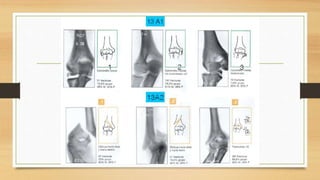

CLASIFICACION AO